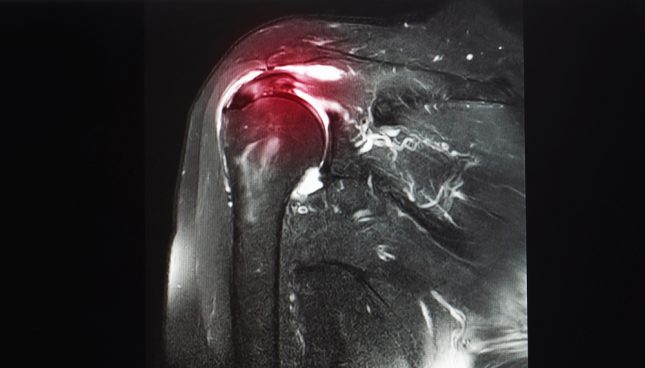

במחקר חתך רב-מוקדי זה, מטופלים עם דלקת פרקים וספחת (שלא נוטלים טיפול שמשפיע על כל הגוף) ופבירומיאלגיה וספחת עברו הערכה קלינית לדלקת בגיד והערכה בעל קול (B-Mode והערכת דופלר) ל-6 זוגות גידים.

כאשר נעשה שימוש בעל קול סימני מעורבות גידית היו נפוצים יותר בספחת ודלקת פרקים עם ספחת (כ–90% בקבוצות אלו ו–75% בקבוצת הפיברומיאלגיה היו לפחות עם גיד אחד מושפע ו–54%, 41% ו–27% מזוגות הגידים בכל אחת מהקבוצות, בהתאמה, הצביעו על לפחות גיד אחד מודלק).